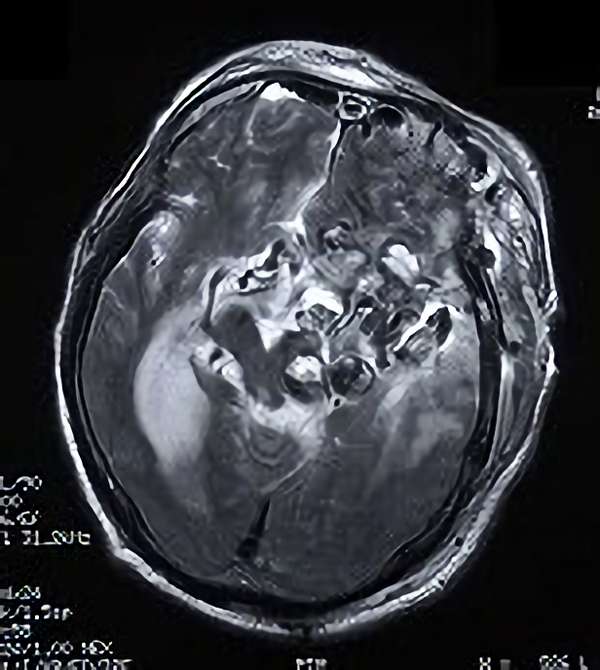

手術前